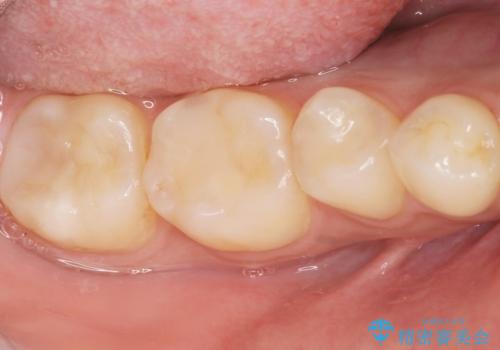

- 奥歯にフロスを通すとにおいがすることを気にされ、来院された患者様です。

精査したところ、奥歯に充填された保険内のコンポジットレジンの適合が悪いことにより、汚れがたまりやすい状態でした。

不適合なレジンを除去し、セラミックインレーによる治療を行いました。(右上76左上67右下7の計5本)